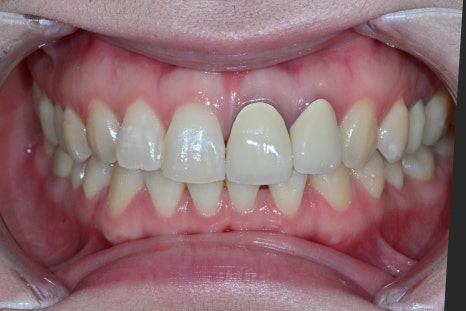

Comparison before and after treatment

<BEFORE>

A female patient in her 30s who recently visited us also

was not satisfied with the color and shape of her existing front-tooth restoration

and wanted a consultation for OBZERO Laminate,

with treatment that was as close to no-prep as possible.

At the first visit

The patient’s existing crown had become discolored,

and the border with the gums was not natural,

so she was always conscious of it in daily conversations

and when taking photos.

At the first visit, a panoramic image and oral photos were taken

to check the overall dental condition,

and because the color, translucency, and symmetry of the front tooth line

had a major impact on the overall impression,

we determined that a design combining laminate and anterior crowns

would be the most suitable.